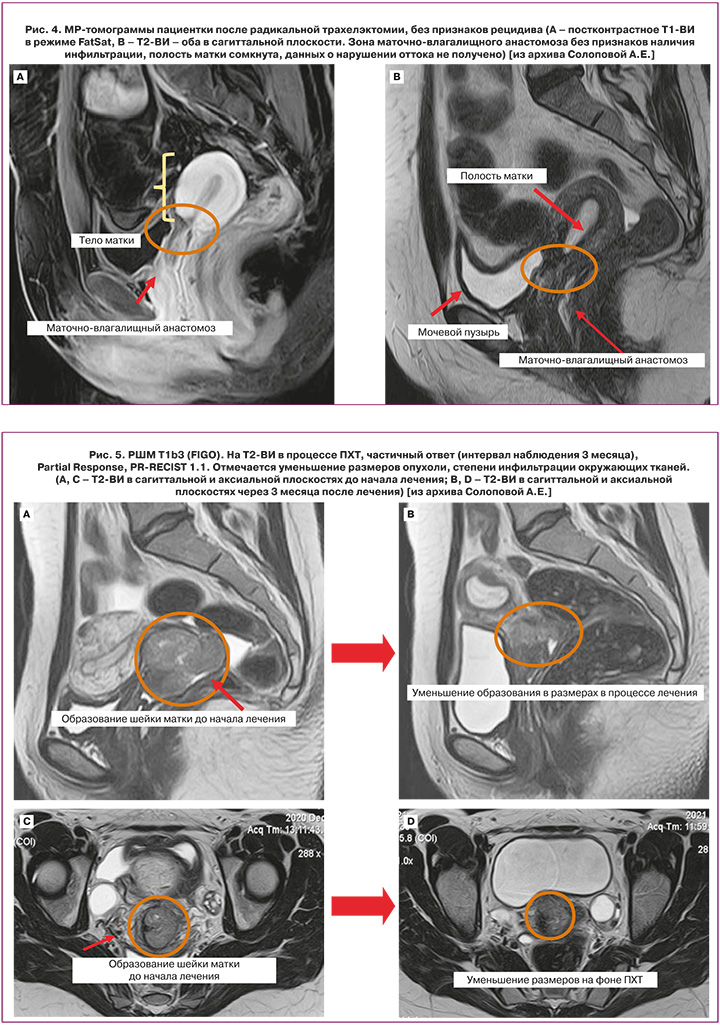

Оценка эффекта от проведенного лечения во многом зависит от его характера, причем точные сроки определены не для всех его вариантов. Согласно рекомендациям ESUR, NCCN, после проведения органосохраняющего хирургического лечения МР-контроль проводится каждые 6 месяцев. При оценке маточно-влагалищного анастомоза после расширенной абдоминальной трахелэктомии помимо исключения рецидива заболевания необходимо исключить наличие осложнений, наиболее важными из которых являются: формирование свищей, стеноз неоцервикса; кроме того – исключение возникновения лимфокист в зоне подвздошной лимфаденэктомии (рис. 4.) В ряде случаев (как один из возможных методов терапии при IB2, IIA2, IIB стадиях) тактика лечения подразумевает проведение НАХТ с последующим выполнением радикального лечения. На рисунках 5–7 представлены варианты ответа опухоли на полихимиотерапию.

МРТ после проведения ХЛТ выполняют через 3–6 месяцев после завершения ХЛТ. Восстановление стромы шейки матки с низкой ИС на Т2-ВИ указывает на полный ответ; при этом сохраняющаяся повышенная ИС в ряде случаев свидетельствует не о наличии остаточной опухоли, а о присутствии отека, реактивного воспаления на фоне развивающихся некротических изменений после проведения лечения, которая может сохраняться до и более 6 месяцев, что определяет ограничения по срокам оценки ответа [35, 36]. При оценке ответа на ХЛТ МРТ позволяет на ранних стадиях прогнозировать неэффективность терапии и в последующем может использоваться для выявления местного рецидива опухоли. Объективный ответ определяется путем оценки размера опухоли и ИС шейки матки. Ответившая на лечение опухоль шейки матки сокращается и замещается зонами фиброзирования и некрозов, что отражается изменением ИС, отсутствием ограничений диффузии в структуре. Некоторые авторы рекомендуют выполнение МРТ через 4 недели после ХЛТ с целью ранней оценки ответа, но большинство учреждений, в т.ч. согласно рекомендациям ESUR, NCCN, рекомендуют проводить ее после завершения лечения через 3–6 месяцев [37].